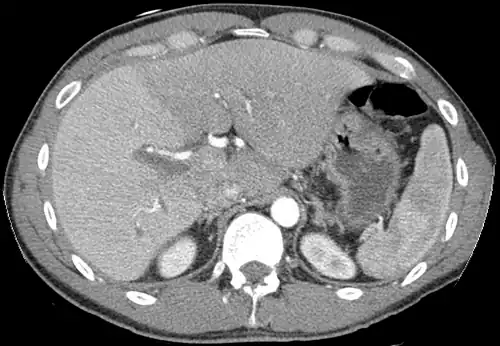

Left lobe liver tumor

The liver is a vital organ and supports almost every other organ in the body. Severe or end-stage liver failure has dire consequences for the body's overall health and quality of life. Visible signs of liver disease include jaundice and ascites. Hepatomegaly refers to an enlarged liver and may be caused by several underlying diseases. It can be palpated in an abdominal exam.

After resection of left lobe liver tumor

Liver transplantation is the only option for those with irreversible liver failure. Most transplants are done for chronic liver diseases leading to cirrhosis, such as chronic hepatitis C, alcoholism, and autoimmune hepatitis. Less commonly, liver transplantation is done for fulminant hepatic failure, in which liver failure occurs rapidly over a period of days or weeks.